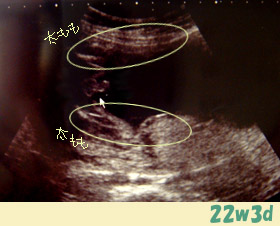

この写真は、赤ちゃんの座っている所を下から撮ったものです。

立派なものがっっっ!!

赤ちゃんの体重:531g

体重:妊娠する前より+7.1㎏(4w前より+2.8)

子宮底長:22cm、腹囲:83cm、血圧:93/41、

今回は、逆子ではなかった。でも一般的に28wまでグルグル動くそうです。

性別・・・男の子

私の耳が確かなら、赤ちゃん24w相当と言われた!